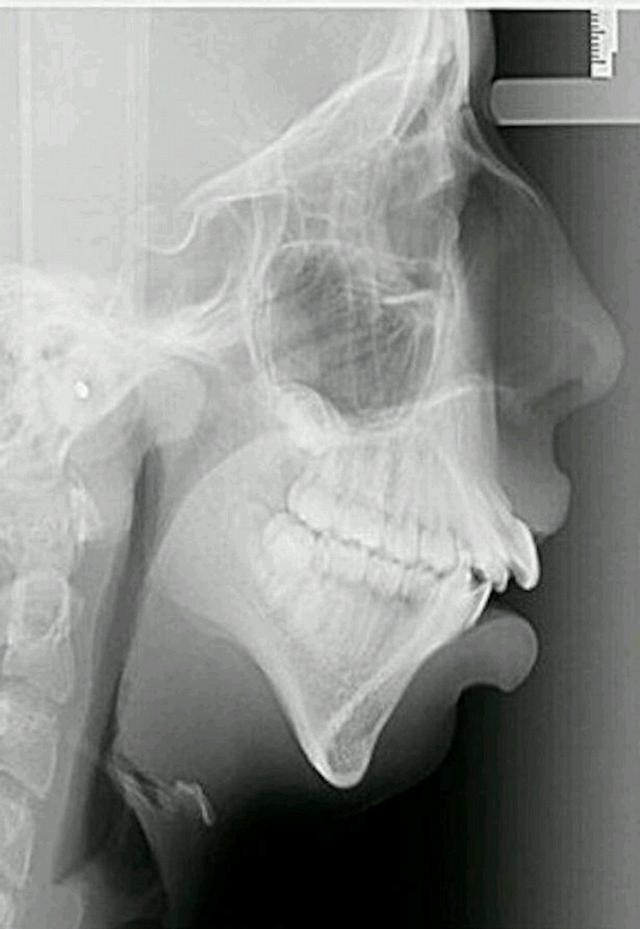

For many years, Ellie used to come to Hickman and Woolley to fix her jaw. And finally after a lot of hard work and dedication to the long-term process, Ellie’s jaw healed and her smile looked beautiful.

Now her surgeries are completed. And she is fully recovered,Ellie has a normal face – and this means the world to the young Ellie Jones.

She lives with her parents and her sister and has grown confidently like a young woman who is proud of the way she looks.

Her parents and teachers have noticed a big improvement in her confidence levels. At her dance class, she used to shy. But now she is confident and eager to show off what she has learned.